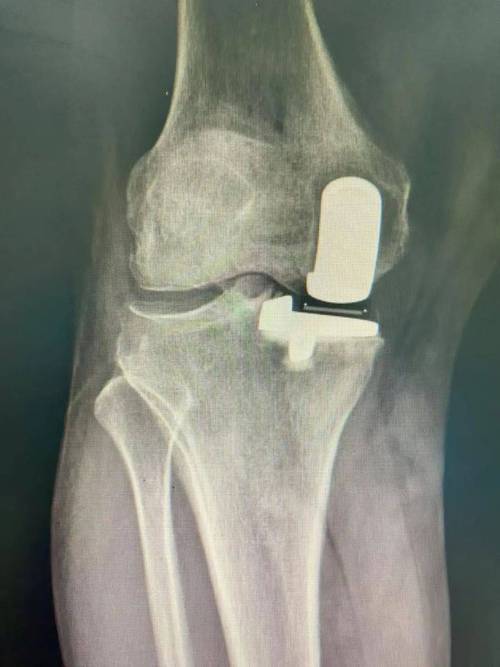

哪些关节最常被置换?

- 膝关节:最常受累、也最常进行置换的关节,严重的RA患者常因膝关节疼痛和畸形而无法行走。

类风湿关节炎患者的关节置换有什么特殊性?

相比于骨关节炎患者,RA患者的关节置换手术有其独特的挑战和考量: